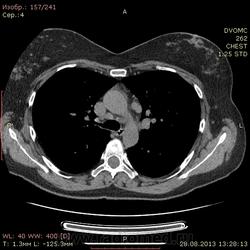

1961 г.р. В течение около 2х недель мучает сильный кашель, температура не поднималась, терапевны назначали антибиотики. Пропила неделю - без какого либо улучшения. Около полутора недель назад делали флюшку - без инфильтративных, корни немного расширены, структурны. Снгодня на флюшке появилась округлая тень слева. Решили сделать КТ - и вот результат.

Множественные мягкотканные мелкие узелки, лимфоаденопатия. Туберкалез? Саркоидоз? Mts? Не знаю чего и думать...прошу помощи.

Лимфапролиферативное заболевание (ЛГМ, лимфома) vs саркоидоз. Нет тут туберкулеза.

1. Внутригрудная лимфоаденопатия. 2.Участки снижения пневматизации легочной ткани по типу "матового стекла". 3. Наличие в обоих легких узелковых образований (гранулем), преимущественно прилежащих к костальной, междолевой и межсегментарной плевре. Комплекс симптомов, наиболее характерен для Саркоидоза легких и ВГЛУ. Показано гистологическое подтверждение: трансбронхиальная внутрилегочная биопсия (информативность до 80% или медиастиноскоия и медистинотомия (информативность до 95%).

На туберкулез легких не похоже.Лимфаденопатия. Метастазы. В меньшей степени вероятен саркоидоз.

Сходила на консультацию к фтизиатрам ставят - саркоидоз...

Предварительно - саркоидоз. Морфоологической небыло пока. Только Пирке сделали...на днях укладывают в стационар и там уж все будет...

Трансбронхиальная биопсия подтвердила диагноз саркоидоза.